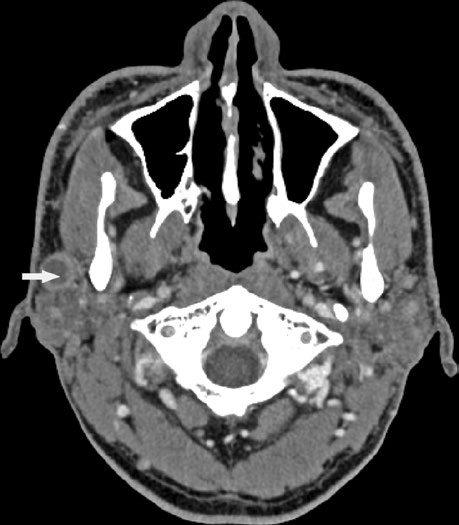

Bone involvement requires specific assessment using bone windows on CT. The image shows periosteal reaction at the posterior aspect of the left mandibular ramus, suggesting direct involvement. When confirmed, the bony structure must be incorporated into the CTV with appropriate margin.

These findings highlight the importance of a thorough imaging study before simulation. The combination of soft tissue and bone windows on the same CT ensures that no tumor extension goes undetected.

When bone involvement is detected, the extent of mandibular irradiation must be carefully balanced against the risk of osteoradionecrosis (ORN). Including the involved bone segment with adequate margin is essential for local control, but extending CTV coverage unnecessarily into healthy mandibular bone increases ORN risk without oncologic benefit. The use of dose painting — delivering higher doses to the involved segment while limiting dose to uninvolved bone — can help achieve this balance when IMRT or VMAT techniques are available.

In my experience, integrating MRI findings — especially fat-saturated sequences — with the simulation CT significantly improves delineation confidence in these complex cases.